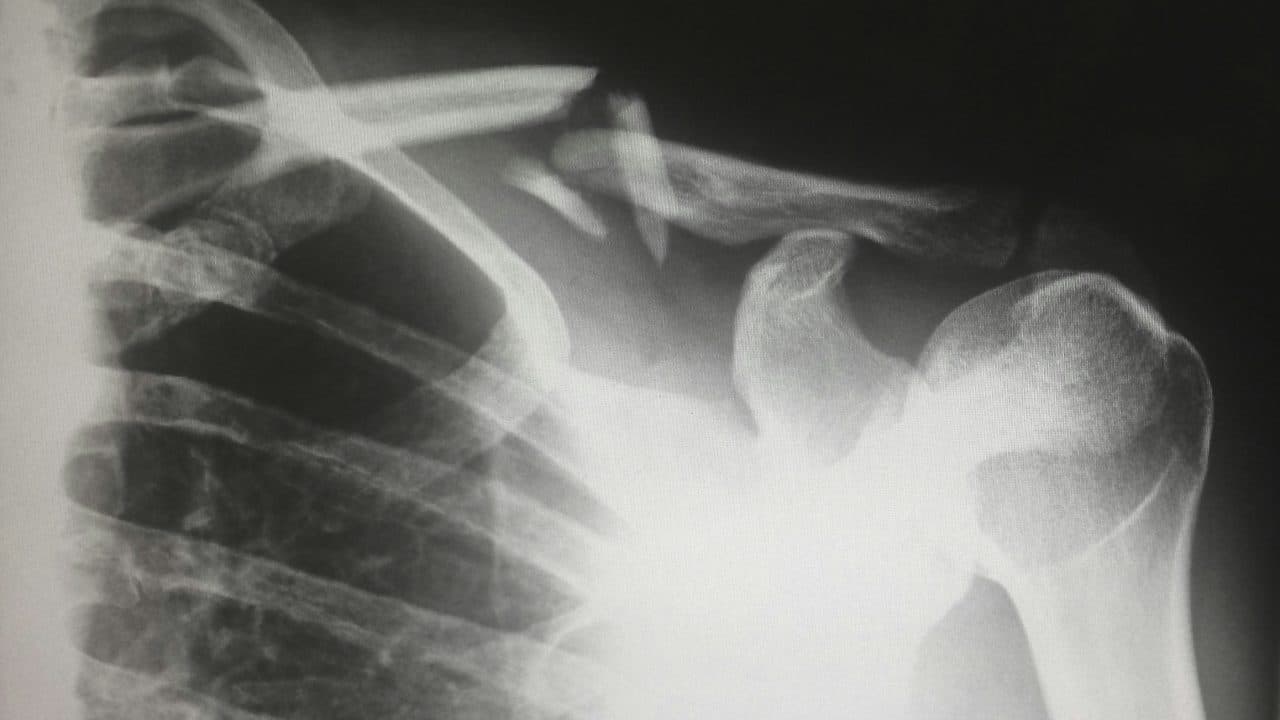

Bone Fractures

Bone fractures are the final type of catastrophic injury that an individual may endure in an accident. Like the other types of catastrophic injuries, bone fractures can range in severity, from partial or hairline bone breaks to partial breaks. Bone fractures are most common in high-impact types of accidents, such as sports, car accidents, or falls from heights. The recovery process for severe bone fractures can be long, often requiring surgery, casting, and physical therapy to help repair and restore the bone and the surrounding muscles and tendons.